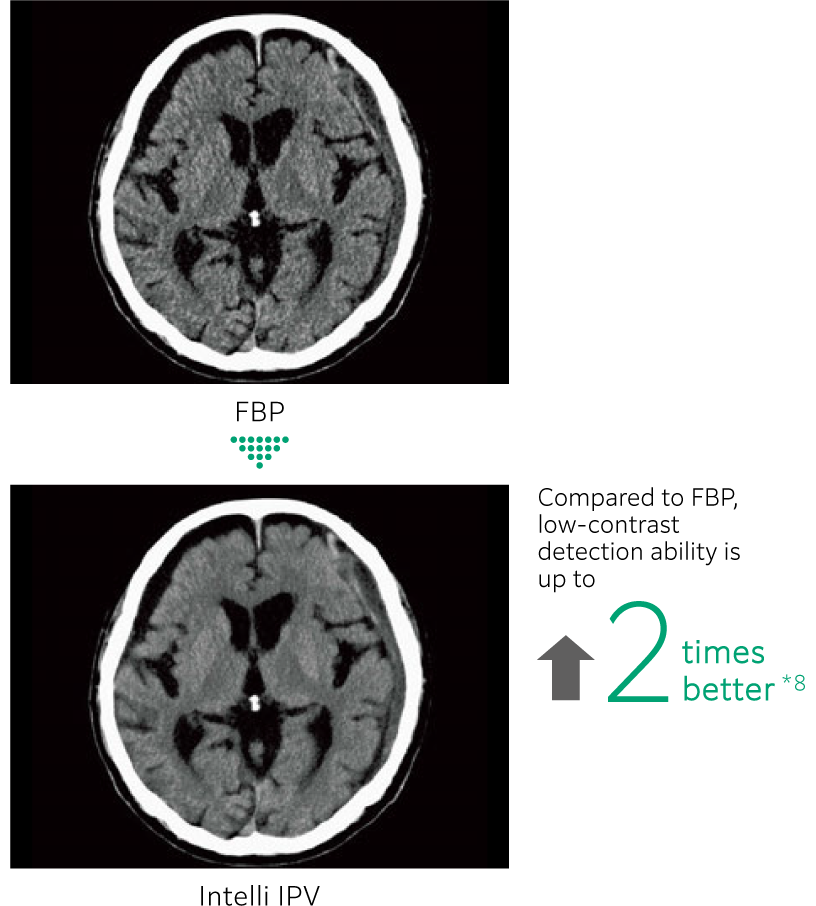

Intelli IPV 是一種利用 AI 技術開發的影像重建技術。透過使用大量經過充分疊代處理的影像作為訓練資料,實現高速且高精度的影像處理,根據富士軟片的視覺模型,使用原始資料的重建處理讓 NPS(雜訊功率頻譜)更接近 FBP(濾波反向投影),即使在高雜訊降低率下也能保持影像紋理, 可實現最高 90% 的影像雜訊*7,以及最高 83%*8的的輻射劑量減少。在低對比檢出能力方面更達到傳統影像處理的 2 倍效果。*8

改善低對比解析度

- *6 Intelli IPV 運用 AI 技術中的機器學習所開發。系統效能與準確性不會隨使用次數自動變化。

- *7 相較於 FBP 其使用 Intelli IPV 強度等級 Strong5 進行測量,並對水假體進行測試。根據臨床任務、病患體型、解剖部位及檢查內容,實際成效可能有所差異。

- *8 相較於 FBP,其使用 Intelli IPV 強度等級 Strong5 以 0.625 毫米的切片厚度進行測量,並使用模型觀測器方法結果,根據 MITA CT IQ 假體 CCT189 假體實驗室進行測試。根據臨床任務、病患體型、解剖位置和臨床檢查,獲得的效果可能較小。